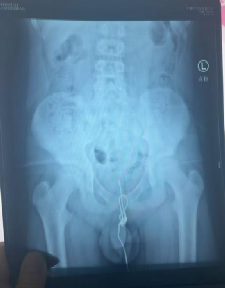

接诊的李一帆博士团队紧急检查后发现,一段30厘米长的橡胶跳绳已进入男孩膀胱并打成死结,滞留近8小时引发急性尿道感染,黏膜布满脓胎,再拖延可能导致膀胱穿孔、影响生殖和肾功能。

医生团队紧急实施腹腔镜微创手术,通过腹部的微小穿刺切口,在腔镜的直视下,小心翼翼地将打结的跳绳剪断,再分段取出。

整个手术过程精准谨慎,尽可能降低创伤,最终成功将跳绳全部取出,术后联合儿外科进行抗感染治疗,目前男孩的病情已经趋于平稳。